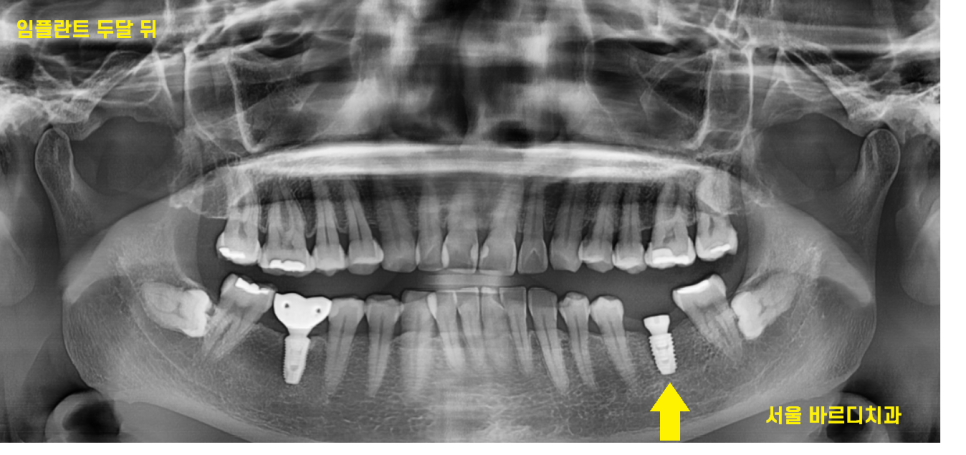

24.03.16

풍산동 임플란트 수술 2달 뒤 사진입니다.

하악 임플란트는 3개월 정도 평균 시간이 걸리지만

뼈가 좋으시니 2달만에 보철을 올렸습니다.

필요없는 뼈 이식까지 진행했더라면

뼈가 만들어지기까지 시간이 필요해

더 오래 걸리셨겠죠?